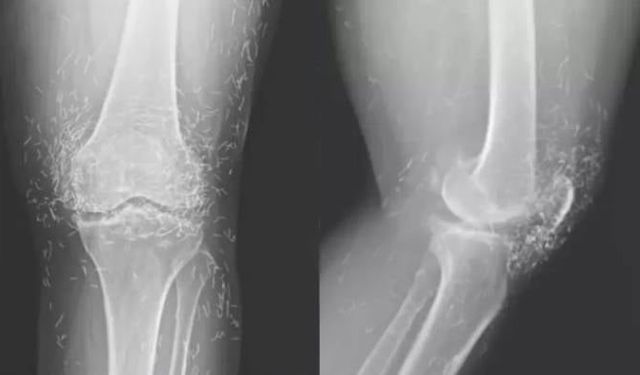

Akciğer kanserinde erken teşhis hayat kurtarıyor

Sağlık